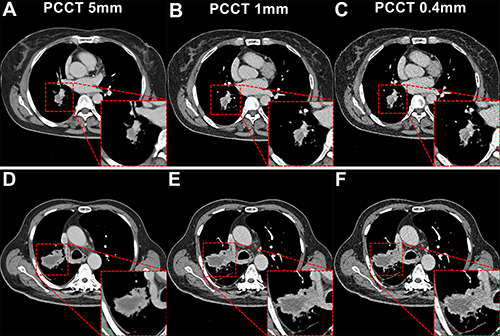

Figure 6. Subgroup analysis based on lesion size on photon-counting CT (PCCT) images. The red outlined areas highlight the magnified images of lesions. (A–C) PCCT images in a 62-year-old woman with a body mass index (BMI) of 23.6, calculated as weight in kilograms divided by height in meters squared, who was diagnosed with adenocarcinoma. A lesion with a long diameter of 25 mm was identified in the right lower lobe on axial images acquired during the venous phase. For lesions less than or equal to 30 mm, decreasing section thickness improved boundary sharpness and contrast between the necrotic area and enhanced tissue, with optimal visualization at 0.4 mm. (D–F) PCCT images in a 66-year-old man with a BMI of 24.2 who was diagnosed with adenocarcinoma, revealing a lesion with a long diameter of 52 mm in the right lower lobe. For lesions greater than 30 mm, a section thickness of 1 mm demonstrated better contrast and clarity at the boundary of the necrotic area compared with 0.4 mm. This observation supported the selection of an appropriate section thickness for accurate quantification of necrotic regions within the lesion.